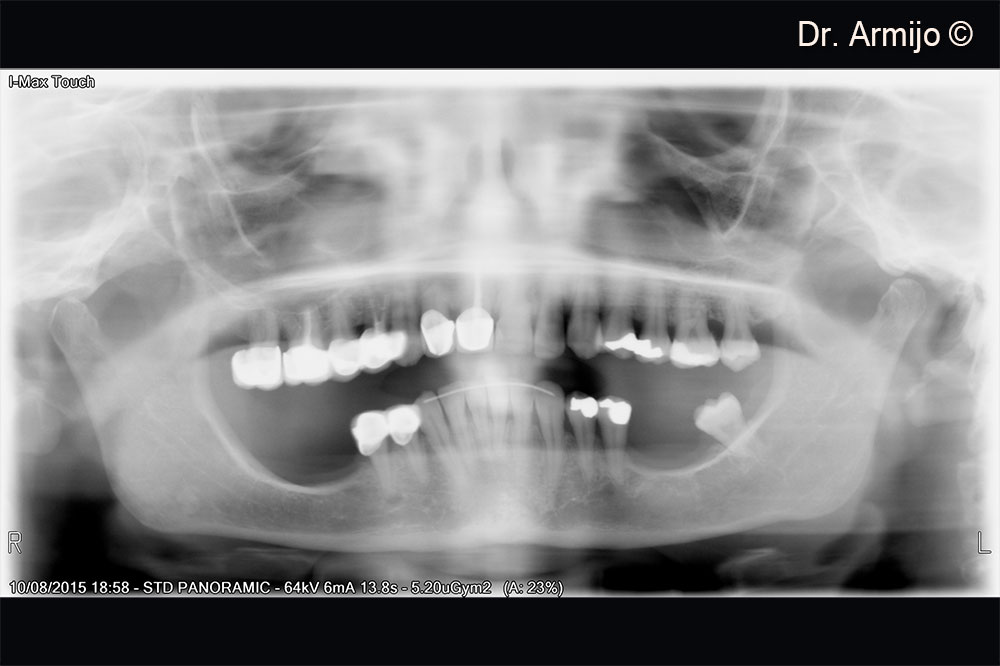

Initial orthopantomography

CT scan visualisation